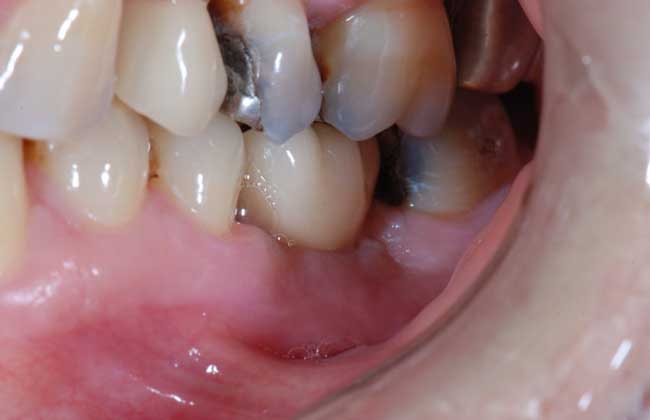

1、功能强大:种植牙齿适合一个或多个牙缺失,能很好地恢复牙齿功能,咀嚼功能大大优于其他传统假牙。

2、不磨牙齿:种植牙齿依靠自身的人工牙根进行修复,不用磨旁边的健康牙齿,对牙齿没有任何伤害。

4、美观协调:种植牙齿可以根据就诊者的脸型、其他牙齿的形状与颜色制作牙冠,达到整体协调和美观的最佳效果。